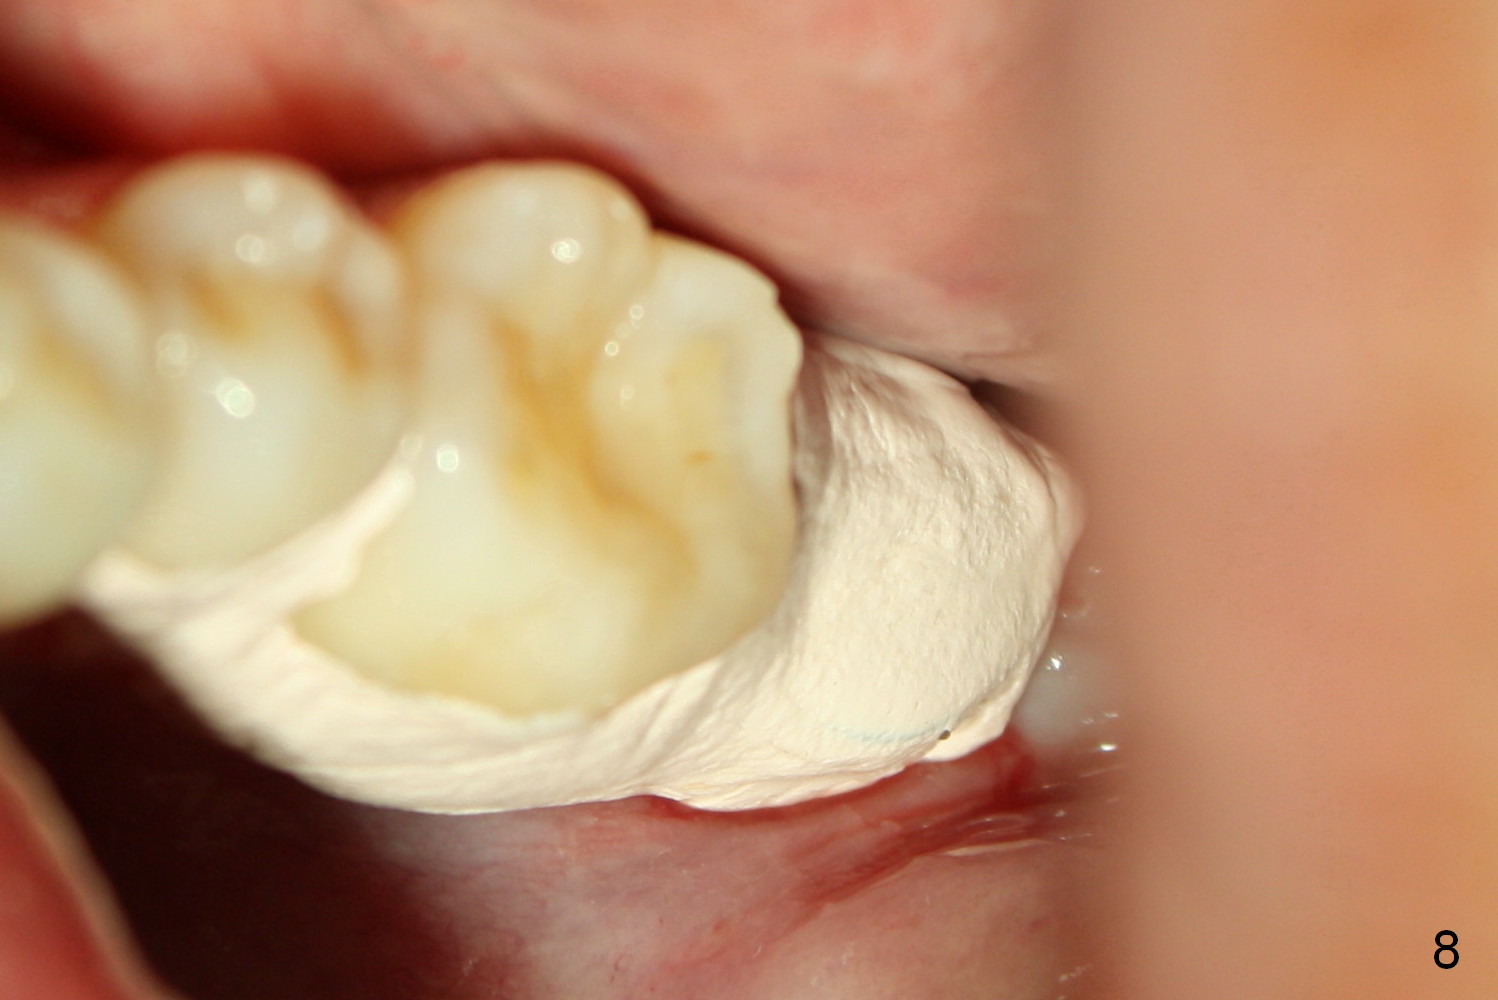

A 48-year-old lady is a dental phobic, requesting extraction of the lower left 2nd molar (Fig.1). She returns for implant placement 9 months post extraction (Fig.2). The ridge is mildly to moderately atrophic. It appears that a 5x12 mm implant is appropriate for the site (Fig.3). For safety, osteotomy is initiated at the depth of 10 mm; it appears that there is enough height for a 12 mm implant (Fig.4). The depth is controlled by drill stopper (Fig.5 S). Finally a 5x12 mm implant is apparently safely placed (Fig.6). A healing abutment is placed and the incision is sutured with 4-0 Chromic gut (Fig.7). Perio dressing is applied around the healing abutment for wound protection (Fig.8). It appears that the healing abutment (Fig.8': *) helps stabilize the perio dressing, which remains in place 1 week postop. When the perio dressing is removed, the wound around the healing abutment is healing (Fig.9). There is no bone loss around the implant 3 months postop (Fig.10 (H: healing abutment), or 16 months postop (i.e., 9 months post cementation, Fig.11,12). The patient complains of pain when she chews with the implant crown, but pain stops whenever she does not bite. Percussion does not elicit any discomfort. The gingiva is healthy. There is possibility of the buccal plate being thin or the lingual plate being perforated in the submandibular fossa. If the discomfort remains the same next 6 months, CBCT will be prescribed.